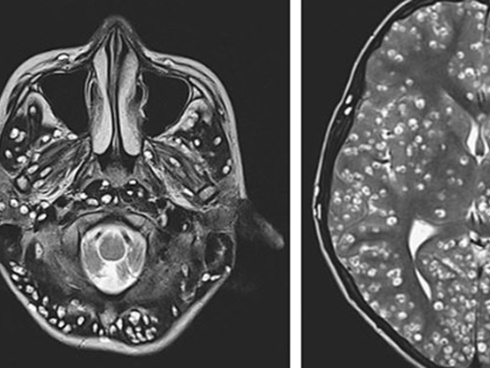

Trong các hình chụp siêu âm, X-quang, có thể nhận ra vô số trứng sán dây (sán xơ mít) cư trú trong cơ thể người đàn ông 74 tuổi. Bệnh nhân này đặc biệt thích ăn thịt lợn và thịt bò tái.

Bác sĩ lập tức chỉ định chụp cộng hưởng từ, chụp cắt lớp vi tính và chụp X-quang cho bệnh nhân. Kết quả, các bác sĩ vô cùng kinh sợ khi phát hiện hàng trăm trứng sán dây nhỏ xíu lúc nhúc trong gần như mọi phần trong cơ thể người bệnh.

Qua hình ảnh chụp chiếu, dễ dàng nhận ra trứng sán dây xuất hiện trong não, cột sống, mông, cổ, ngực và chân cụ ông đã về hưu. Cụ được chẩn đoán mắc bệnh ấu trùng sán lợn. Đây là bệnh nhiễm trùng sán dây, thường là hậu quả của việc ăn thịt lợn bị nhiễm sán.

Hình ảnh chụp cho thấy các u nang ở cổ và ngực.

Tiến sĩ Ming-Pin Lin, một trong các tác giả viết về trường hợp của bệnh nhân 74 tuổi trên, cho biết, hình chụp chiếu thể hiện rõ "một bầu trời đầy sao" ấu trùng sán và còn tiết lộ cả tình trạng vôi hóa của cơ. Tiến sĩ chia sẻ thêm, biện pháp điều trị bao gồm thuốc kháng ký sinh trùng, steroids và đặt thiết bị vào não để giảm áp lực lên não gây ra bởi hiện tượng ứ dịch.

Hình ảnh trứng sán dây ở cột sống thắt lưng và mông, các chấm trắng cho thấy cụm trứng sán dây trong não của bệnh nhân